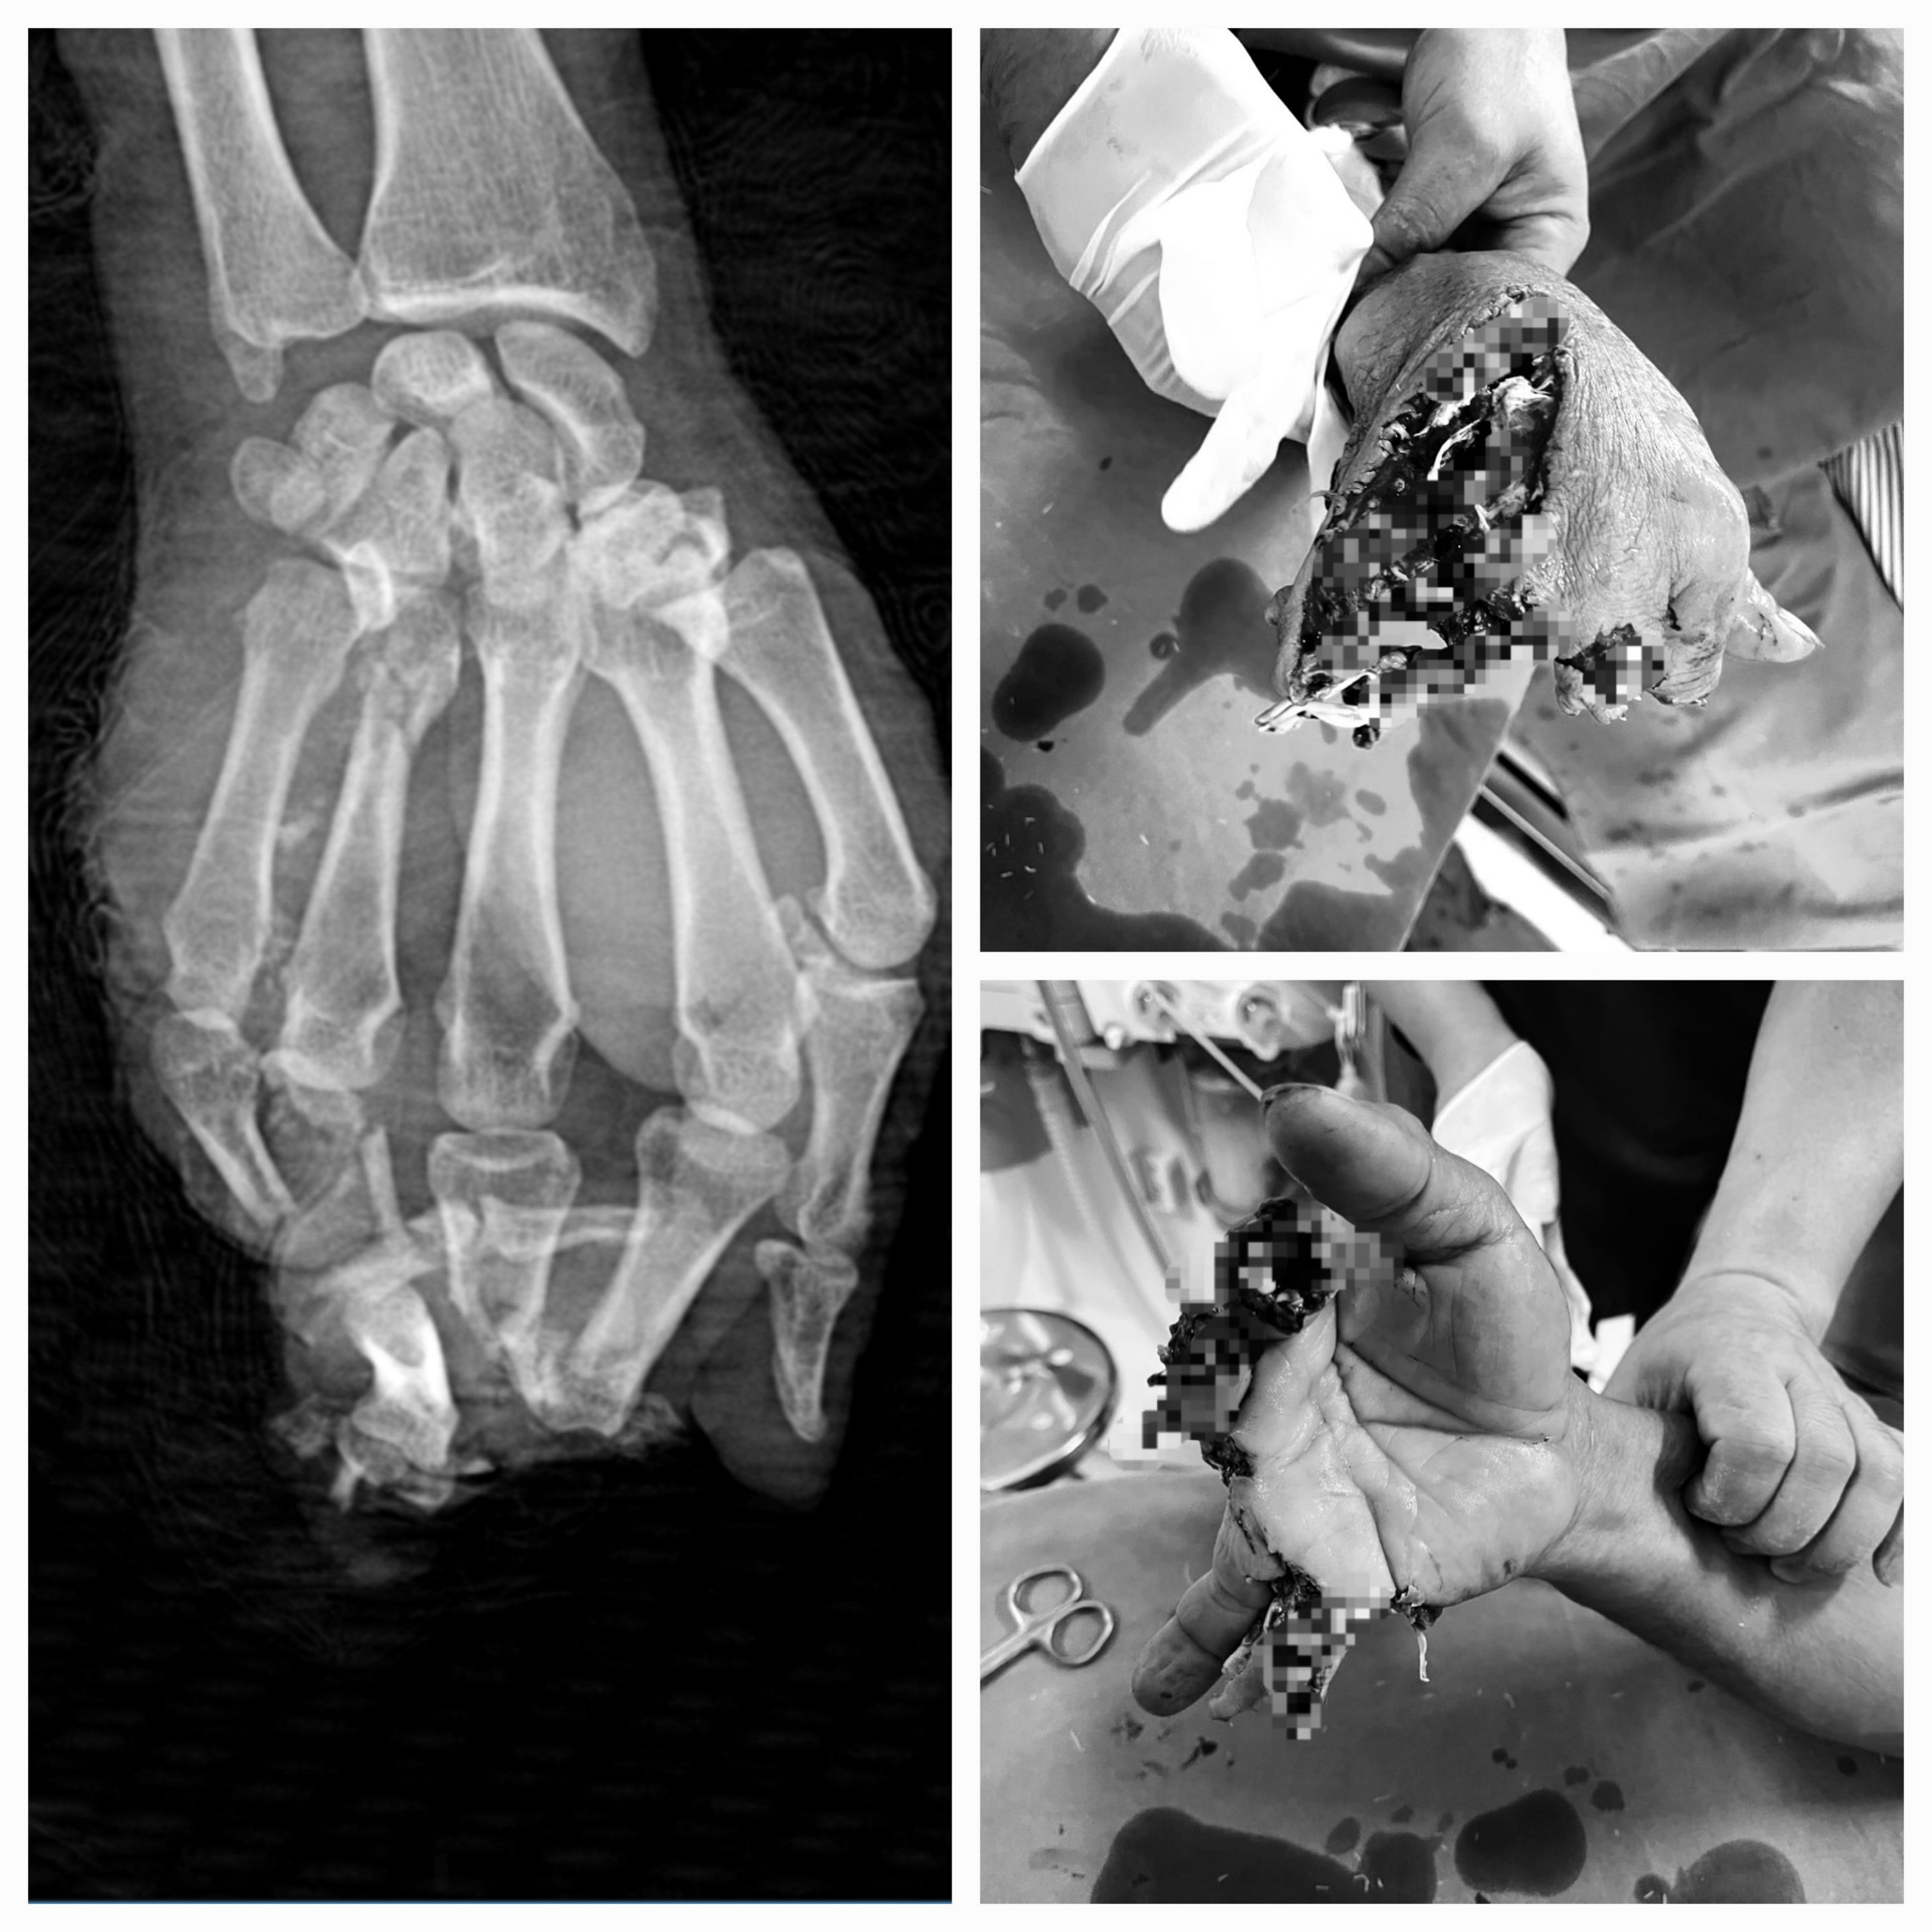

Hình ảnh vết thương của BN sau tai nạn LĐ

Nam bệnh nhân (ở xã Phúc Sơn, huyện Lâm Bình) bị máy bào cắt vào bàn tay phải. Được người nhà đưa đến TTYT huyện Chiêm Hóa trong tình trạng ngón 2, 3,4,5 bàn tay phải vết thương dập nát hoàn toàn, mất ngón, khuyết da che phủ phần mềm, chảy máu.

Bệnh nhân nhanh chóng được cầm máu, cố định vết thương và chuyển phẫu thuật ngay sau đó. Theo đó, các Bác sĩ đã tiến hành cắt lọc bơm rửa lấy hết dị vật trong vết thương, cắt lọc tổ chức dập nát làm sạch vết thương, tạo mỏm cụt các đầu chi, cắt lọc bảo tồn gân, cố định xương gãy ở tư thế chức năng, khâu nối lại hệ thống gân bị đứt…

Sau 02 giờ tiến hành ca phẫu thuật thành công, bệnh nhân trong tình trạng ổn định và đang được chăm sóc, theo dõi tại khoa ngoại.